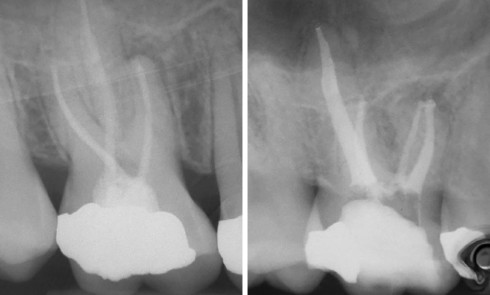

Endodontie

Article réservé à nos abonnés Les douleurs postopératoires en endodontie

Situations difficiles Dans la suite de notre numéro post ADF, paru le 31 janvier dernier, nous avons rassemblé les comptes rendus...